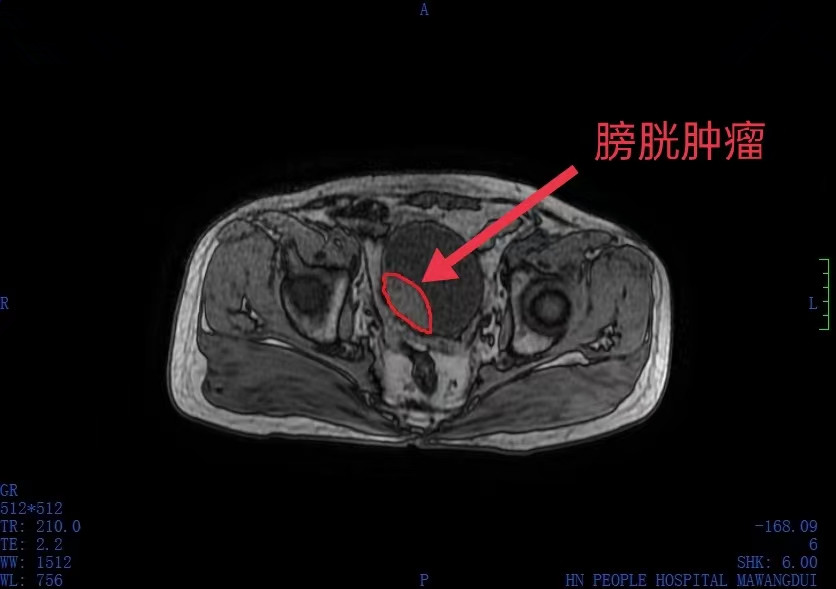

肖大爷半年前出现尿频尿急尿痛、夜尿增多的情况时,觉得去医院很麻烦,就自己上网查了一下,发现症状与前列炎增生和泌尿系统感染很相似,于是购买了抗前列腺增生的药和消炎药,刚开始效果还不错,但后来药物越来越不起作用,之前的症状不但没有缓解,反而出现了血尿现象,才引起重视。到当地医院经CT检查发膀胱右侧后壁有一肿块,考虑膀胱癌,为寻求进一步治疗,到捷克论坛 泌尿四病区就诊。

入院后,泌尿四病区杨科主任团队为肖大爷做膀胱镜检查,发现因为就医时间较晚,肖大爷的膀胱肿瘤已经浸润到膀胱肌层,只能手术将整个膀胱切除,再取一段回肠进行裁剪,将两侧输尿管缝合在回肠上,用它来替代切除的膀胱储存尿液,最后在腹壁上开一个造瘘口引流出尿液,也意味着肖大爷腹部得终身佩戴一个造瘘袋收集尿液。手术顺利完成,肖大爷经过一段时间的康复,于今日出院。